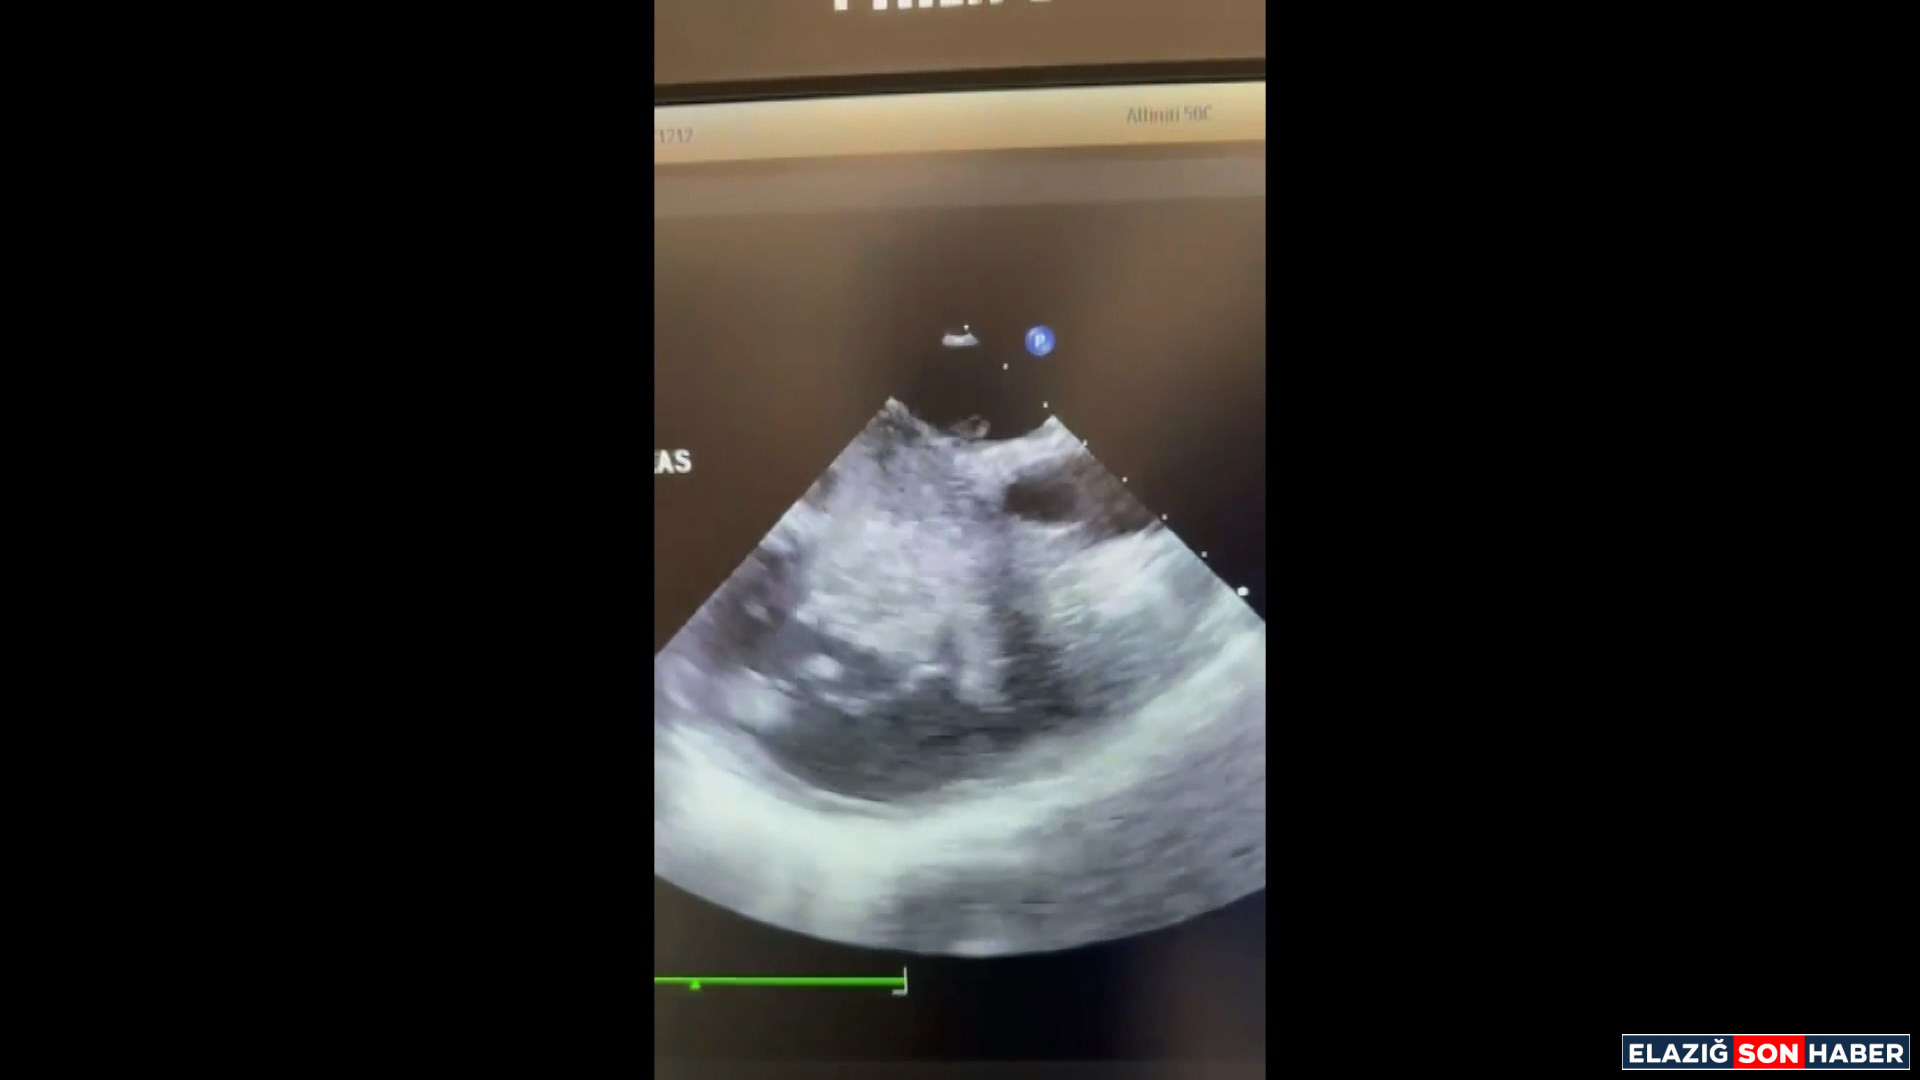

Nefes darlığı ve sırt ağrısı şikâyetleriyle Elazığ Fethi Sekin Şehir Hastanesi Acil Servisi’ne başvuran yabancı uyruklu 22 yaşındaki Mutemenna Necib’e yapılan tetkikler sonucunda pulmoner emboli tanısı konuldu. Embolinin kaynağını belirlemek amacıyla yapılan Bilgisayarlı Tomografi ve EKO incelemelerinde, kalbin neredeyse tamamını dolduran büyük bir kitle tespit edildi.